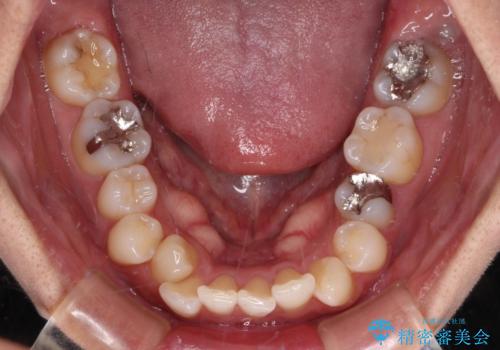

- 前歯のクロスバイトと口元の膨らんだ横顔の印象を気にして来院された患者様です。

しかしながら。そのまま叢生を解消すると横顔が突出した印象になる可能性が高かったため、上下左右の小臼歯4本を抜歯して、ワイヤー装置にて矯正治療を行うこととしました。

上下左右の第一小臼歯4本を抜歯して治療を行うことがセオリーでしたが、左下は第二小臼歯が銀歯であったため、イレギュラーではありますが、そちらを抜歯しました。

その影響で治療期間は長くなりましたが、処置していない歯を保存することができました。